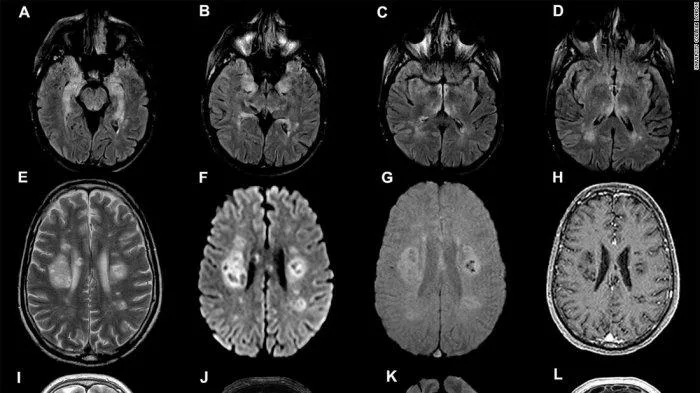

Ujian Kognitif

Kajian yang diketuai oleh Adam Hampshire, seorang doktor dari Imperial College London telah memeriksa 840,000 pesakit yang diminta untuk melakukan ujian kognitif bagi mengesan kekuatan otak. Mereka mendapati bahawa beberapa kes yang serius, Covid-19 boleh dikaitkan dengan penurunan kemampuan kognitif. Ini akan berlanjutan selama beberapa bulan setelah pesakit sembuh.

Antara ujian yang dilakukan adalah seperti menghafal perkataan, menghubungkan titik, ujian teka teki dan sebagainya. Ujian seperti ini biasanya akan digunakan oleh doktor untuk mengesan sama ada terdapat gangguan otak atau tidak atau tanda-tanda penyakit Alzheimer.

Pesakit Mengalami Penuaan Otak Sehingga 10 Tahun Lebih Awal

Menurut Reuters, setelah pesakit melakukan ujian kognitif, pasukan penyelidik mendapati terdapat banyak penurunan fungsi otak pada pesakit Covid-19 yang dirawat di Hospital atau Pusat Rawatan.

Kes terburuk menunjukkan bahawa kognitif mereka telah menurun setara dengan penuaan otak mereka iaitu 10 tahun lebih awal.